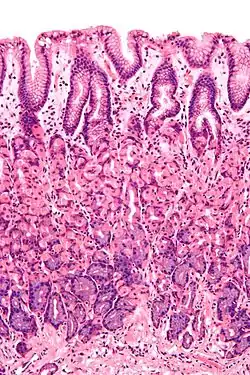

The epithelium, the most exposed part of the mucosa, is a glandular epithelium with many goblet cells. Goblet cells secrete mucus, which lubricates the passage of food along and protects the intestinal wall from digestive enzymes. In the small intestine, villi are folds of the mucosa that increase the surface area of the intestine. The villi contain a lacteal, a vessel connected to the lymph system that aids in the removal of lipids and tissue fluids. Microvilli are present on the epithelium of a villus and further increase the surface area over which absorption can take place. Numerous intestinal glands as pocket-like invaginations are present in the underlying tissue. In the large intestines, villi are absent and a flat surface with thousands of glands is observed. Underlying the epithelium is the lamina propria, which contains myofibroblasts, blood vessels, nerves, and several different immune cells, and the muscularis mucosa which is a layer of smooth muscle that aids in the action of continued peristalsis and catastalsis along the gut.

- In the stomach, the epithelium is simple columnar, and is organised into gastric pits and glands to deal with secretion.[1]

- In the small intestine, epithelium is simple columnar and specialised for absorption. It is organised into plicae circulares and villi, and the enterocytes have microvilli. The microvilli create a brush border that increases the area for absorption. In the ileum there are occasionally Peyer's patches in the lamina propria. Brunner's glands are found in the duodenum but not in other parts of the small intestine.[1]

Cross-section histology of intestinal villi of the human terminal ileum.